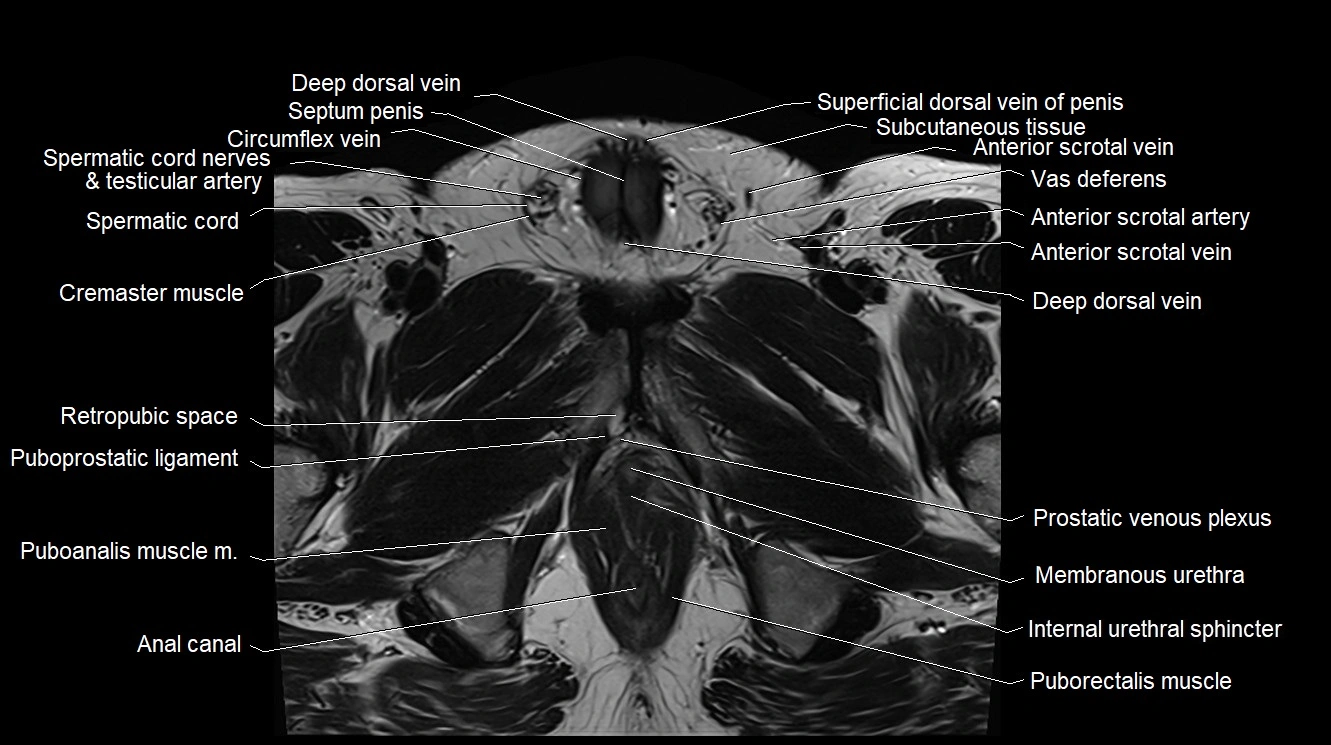

- Deep dorsal vein of penis

- Deep dorsal vein of the penis

- Septum of the penis (Penile septum)

- Cremaster muscle

- Spermatic cord

- Spermatic cord nerves

- Retropubic space

- Puboprostatic ligament

- Puboanalis muscle

- Puborectalis muscle

- Membranous urethra

- Internal urethral sphincter (male)

- Anal canal

- Vesical venous plexus